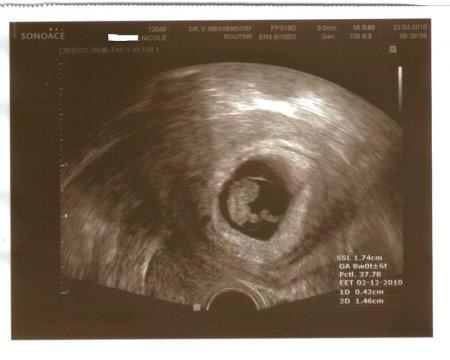

Heute endlich kann ich Euch in Ruhe berichten wie am Donnerstag der Fa Termin verlief. Zunächst einmal: ich muss immernoch liegen und habe immernoch eine Blutung und Gewebeabgänge, aber unser Flöckchen beeindruckt das überhaupt garnicht! Es wächst stur weiter wie ein Panzer auf Kurs und wir sind total stolz auf das Kleine! Ich muss nun alle 14 Tage zum Fa (zwischendrin war ich auch im Krankenhaus). Nächster Termin: 07.05. UND ich habe meinen ERSTEN MAMAPASS bekommen!!!! Das hat mir auch unendlich viel bedeutet, weil ich bei allen anderen Schwangerschaften es nie bis hierher geschafft hatte und ich auch diesmal gezittert habe, ob man ihn mir ausstellt. ET ist immernoch 30.11.2010. Die US-Fotos von Flöckchen bei 8+2 habe ich angehängt. Die Fehlgeburt droht immernoch aber ich bin wesentlich zuversichtlicher geworden und hoffe ich komme recht schnell nun in die 13 Woche. Mit Übelkeit und Kopfweh,Kreuzschmerzen muss ich mich auch im Augenblick noch herumschlagen, aber das ist peanuts. Solange es Flöckchen gut geht, ist mir alles andere völlig wurscht. Am Montag muss ich nun zur Gerinnungsambulanz und dann kann man hoffentlich was gegen die Blutung unternehmen. Mein TSH (Schilddrüse) ist wunderschön auf 1,16 gefallen und die Antikörper (Hashimoto) sind wirklich total niedrig -machen also im Moment keine Schwierigkeiten. Also kann ich alles in allem sagen: UNS GEHT ES SUPER für die Umstände. Ich möchte allen ganz lieb Danke sagen für die Daumen und alle lieben Wünsche SIE HABEN GEHHOLFEN!! BITTE WEITER DAUMEN DRÜCKEN IHR SEID MIT ZAUBERDAUMEN GESEGNET! Alles Alles Liebe Nicole / Feenstaub226

FLöckchen mit Nabelschnur - ein/e echte/r Astronaut/in!

Bild zu